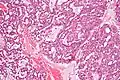

| Low magnification micrograph of a polymorphous low-grade adenocarcinoma, showing the typical variation of architectural arrangement. H&E stain. | |

PLGAs consist of a monomorphous cell population that has a varied histologic morphology.

Microscopically, its histology can be confused with an adenoid cystic carcinoma and a pleomorphic adenoma.